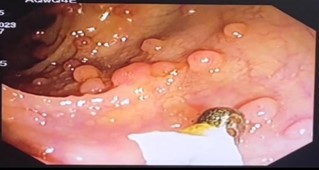

Fig. A – Pedunculate polyp

Fig. B and C show a Colonoscopic picture of both sessile and pedunculated Polyp

- A colonoscopy revealed a concerning finding of multiple pedunculated and sessile colonic polyps, exceeding 100 in number, spanning from the rectum to the cecum.